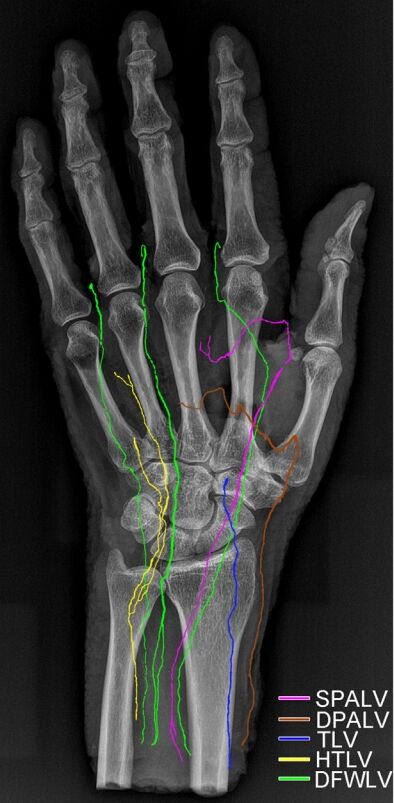

徐州医科大学解剖教研室潘伟人教授的文章图片

X线片都如此清晰

比临床片子都要清楚